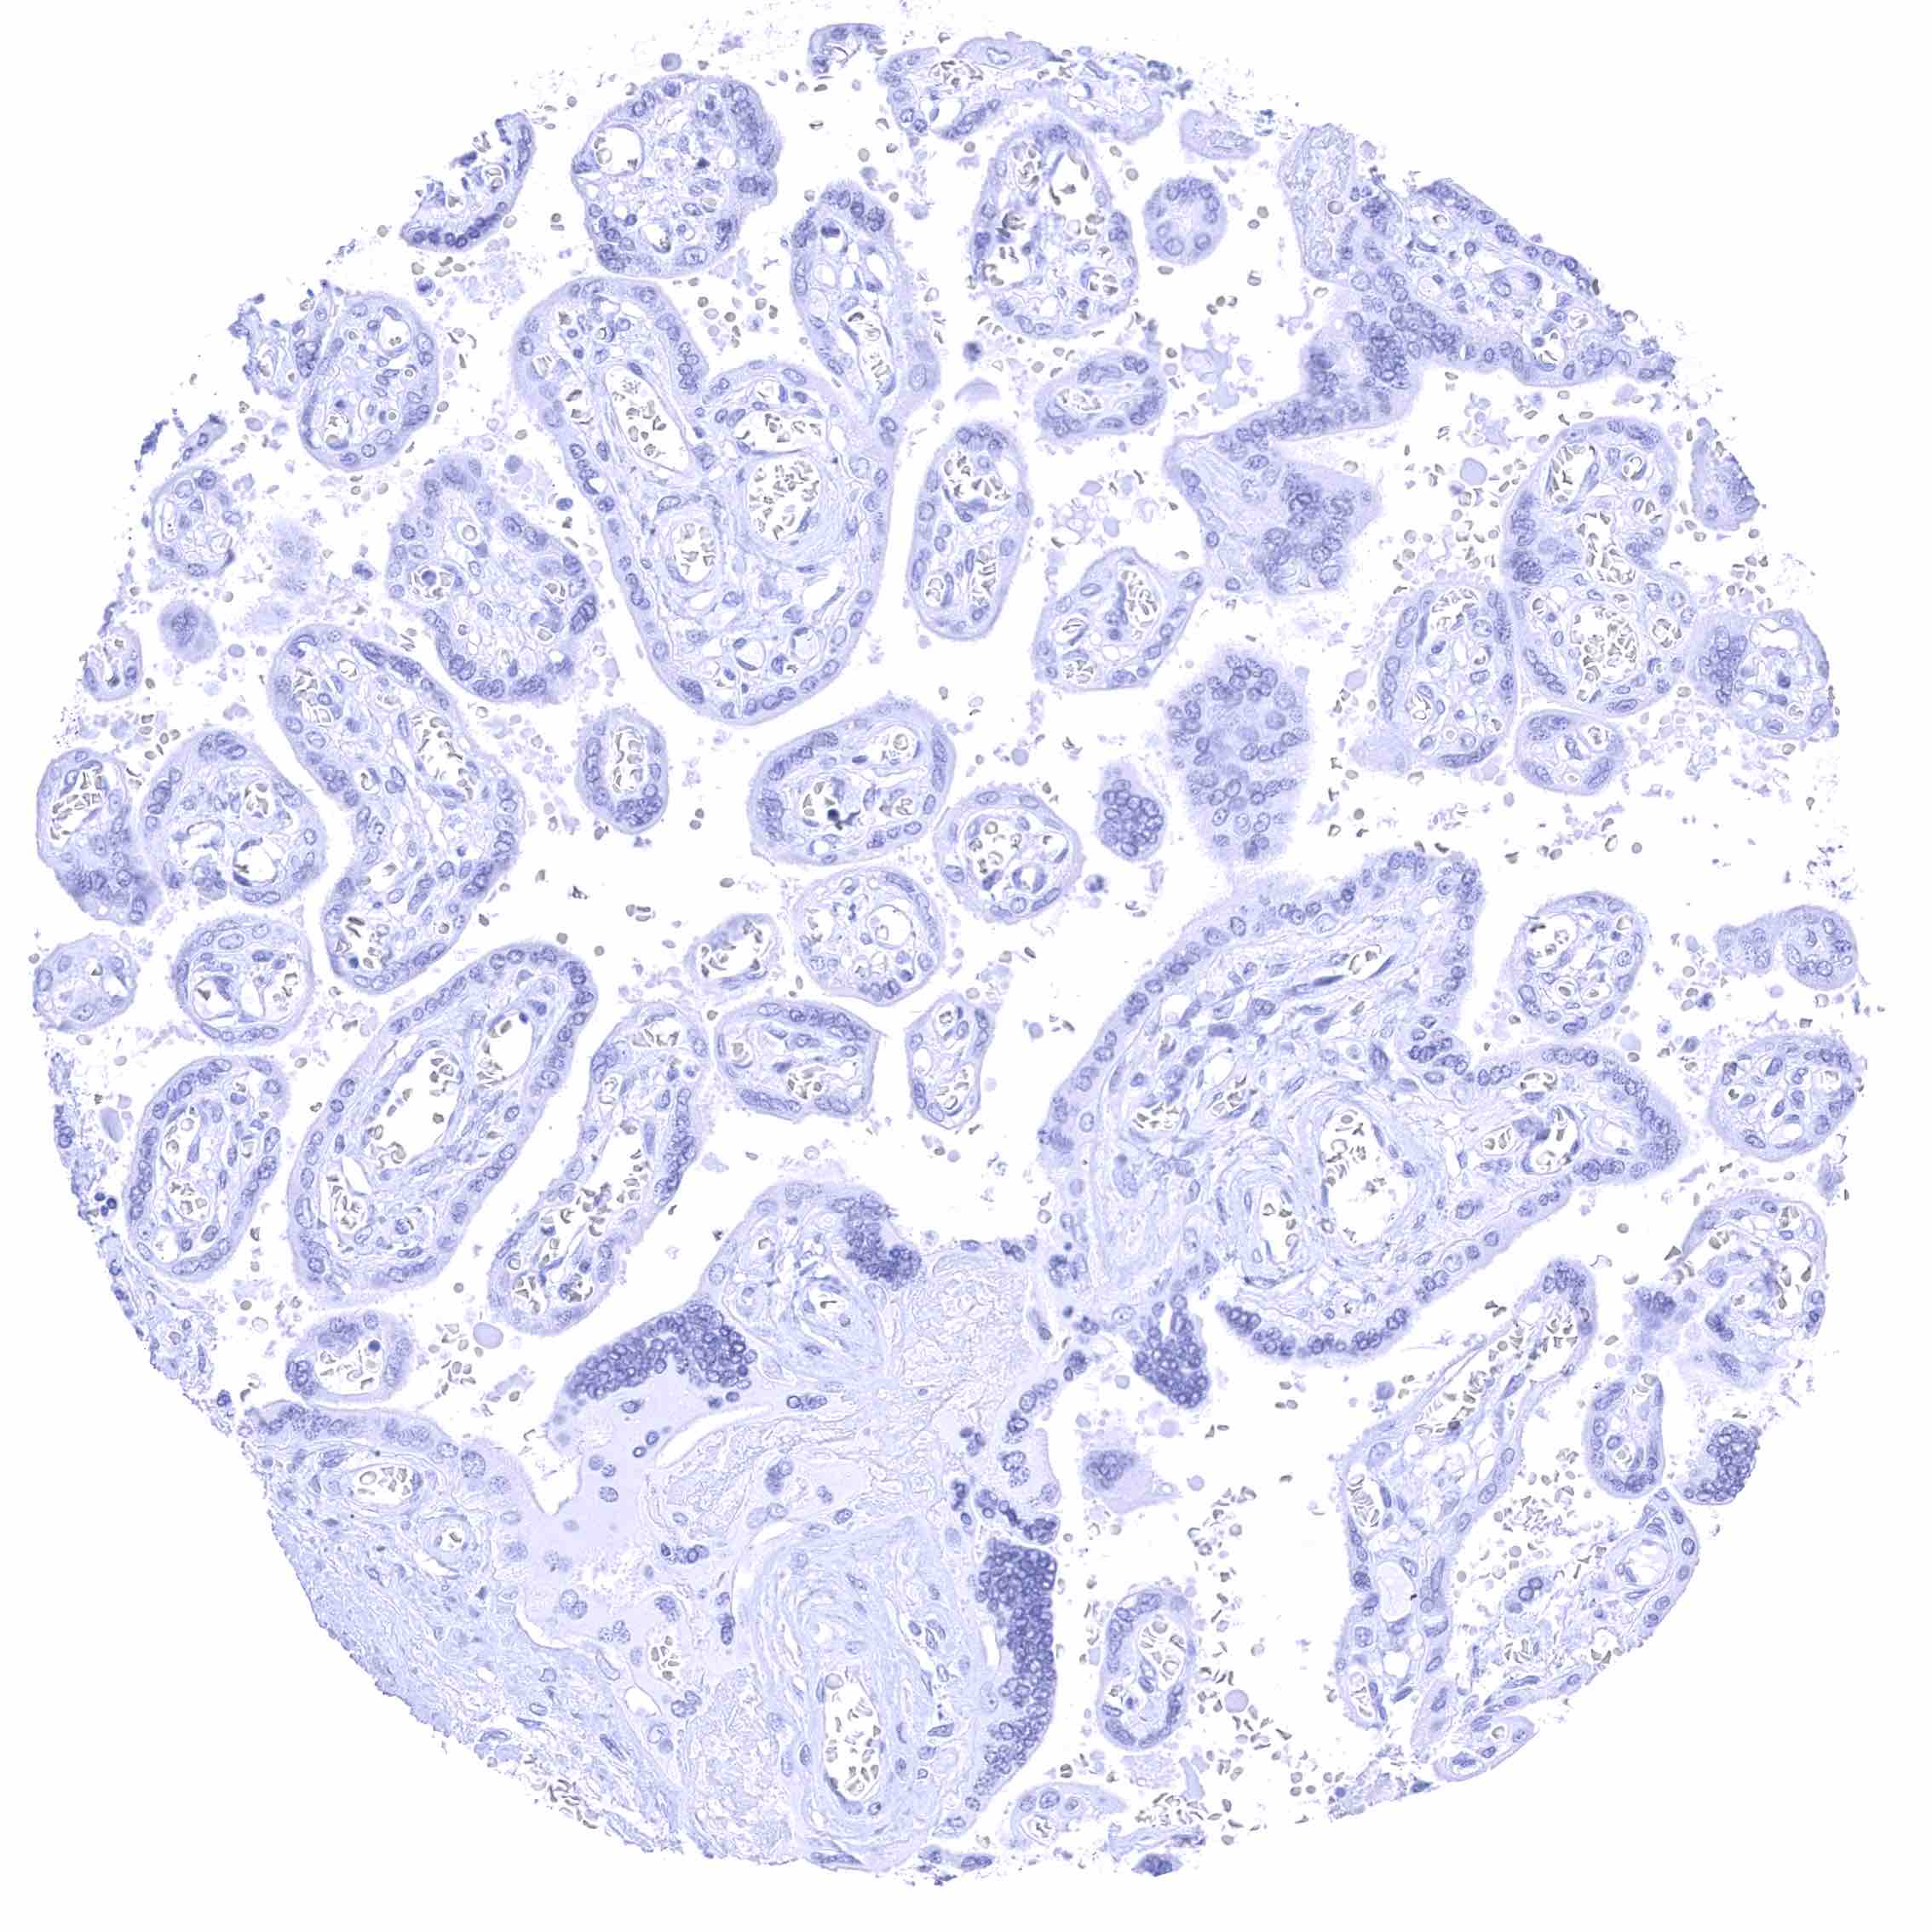

Placenta (amnion and chorion)

Placenta, early

Placenta, mature